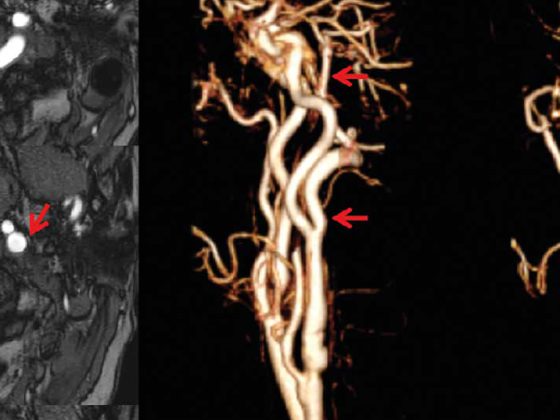

Komplizierte Nierenzysten